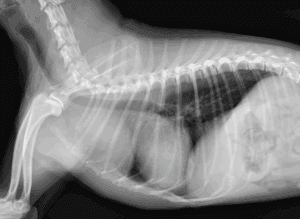

犬のインスリノーマ

犬のインスリノーマ(膵島β細胞腫瘍)は、膵臓のβ細胞が腫瘍化し、必要以上にインスリンを分泌してしまう腫瘍です。インスリンが過剰に出続けると、血糖値の低下(低血糖)を引き起こし、さまざまな臨床症状が引き起こされます。低血糖 […]